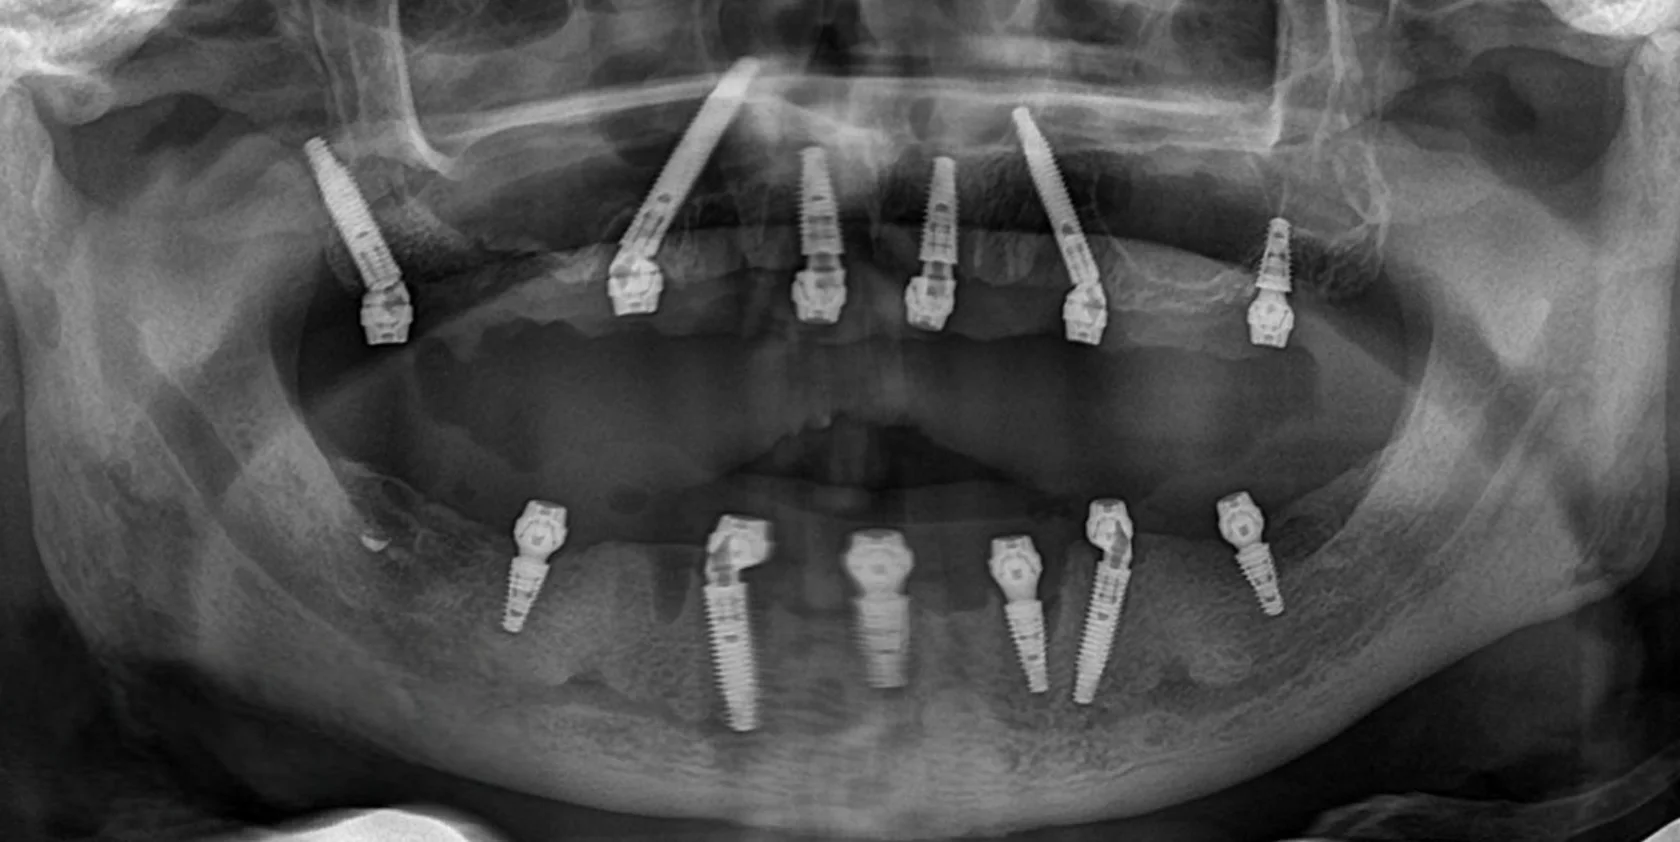

«Говорили, что это невозможно». Пациентка долго слышала, что в её ситуации полноценное восстановление зубов невозможно или потребует множества этапов и длительного лечения. Это останавливало её от решения проблемы на протяжении многих лет. Частичное отсутствие зубов на верхней и нижней челюсти требовало функционального и предсказуемого решения.

На консультации мы провели подробную диагностику и нашли варианты лечения. В итоге была выполнена тотальная реабилитация. В день операции установлены имплантаты и несъёмные конструкции.

Уже через 4 часа была восстановлена жевательная функция и anti-age-эффект за счёт правильной опоры мягких тканей.

Долгое время пациентка стеснялась улыбаться и избегала фотографий из-за проблем с зубами и неудобных съёмных конструкций. Она откладывала лечение, считая, что восстановление будет долгим и тяжёлым. Отсутствие зубов на верхней и нижней челюсти требовало надёжного и долгосрочного решения.

На консультации мы подробно обсудили все варианты и выбрали современное и комфортное решение. Было выполнено полное восстановление зубных рядов по концепции All-on-6 с немедленной нагрузкой. В день операции установлены имплантаты и несъёмные протезы.

Сегодня пациентка улыбается уверенно, свободно общается и возвращается к привычной активной жизни без прежних ограничений.

Пациент долго откладывал лечение, сомневаясь в необходимости серьёзного вмешательства и опасаясь сложной операции. Но со временем неудобства и ограничения в повседневной жизни, особенно во время приёма пищи, стали перевешивать сомнения.

На консультации мы подробно разобрали все этапы лечения, обсудили возможные риски и подобрали понятный и комфортный план. В итоге была проведена реабилитация верхней и нижней челюсти по концепции All-on-6 с немедленной нагрузкой. В день операции установлены имплантаты и несъёмные конструкции.

Сегодня пациент признаётся, что зря так долго сомневался — результат превзошёл его ожидания.

Долгие годы жил без полноценного зубного ряда из-за страха большой операции. На консультации всё очень подробно рассказали и убедили, что процесс будет комфортным и не вызовет неприятных эмоций.

Провели реабилитацию верхней и нижней челюсти по концепции All-on-4 с немедленной нагрузкой. В день операции установлены имплантаты и несъёмные протезы.

Теперь точно все страхи позади. Пациент улыбается уверенно и ест без ограничений.

Долгое время откладывал лечение, потому что боялся сложной операции и долгого восстановления. Жил с постоянным дискомфортом и ограничениями в питании, но не решался сделать первый шаг. Длительное отсутствие зубов на верхней и нижней челюсти привело к потере жевательной эффективности и опоры мягких тканей.

На консультации мы подробно разобрали все этапы лечения, ответили на все вопросы и подобрали комфортный и безопасный план. По протоколу All-on-4 на обеих челюстях установлены несъёмные конструкции.

Уже в день операции пациент получил новую улыбку. Обеспечена стабильность прикуса, полноценная функция и выраженное улучшение лицевых пропорций за счёт восстановления опоры тканей.